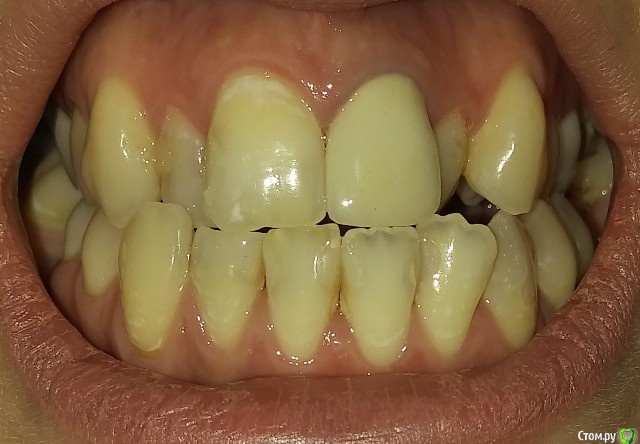

Есть рецессии на нижних зубах и на верхнем клыке слева и резорбция. Ортодонты говорят, что это последствия неправильного прикуса, травмирующего смыкания и с брекетами все стабилизируется, но из-за движения зубов может и усугубиться, как повезет. Вестибулопластику никто не предлагал, а один вообще сказал, что в моем случае она бесполезна. У хирурга-парадонтолога другое мнение: нужно сделать сначала операцию на нижних зубах (углубить преддверие, устранить тяжи и положить какой-то там замещающий материал), а потом поставить брекеты, иначе без операции брекеты спровоцируют еще большее оголение и рецессии станут просто огромными.  А после брекетов уже закрывать, если нужно, рецессии.  Прошу поделиться вашим мнением? В чем причина рецессий и резорбции? Поможет ли в моем случае вестибулопластика?